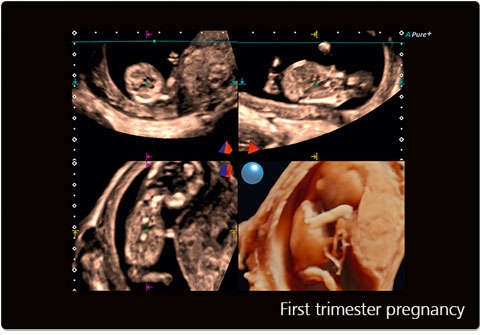

• STIC - исследование сердца плода в режиме объёмной визуализации

• STIC Color - цветная объёмная визуализация сердца плода

STIC:

Да

STIC Color:

• Трехмерная эхография в реальном времени с использованием специализированных 4D датчиков;

• Программа анализа сердца плода в трех проекциях в реальном времени 4D Stick;